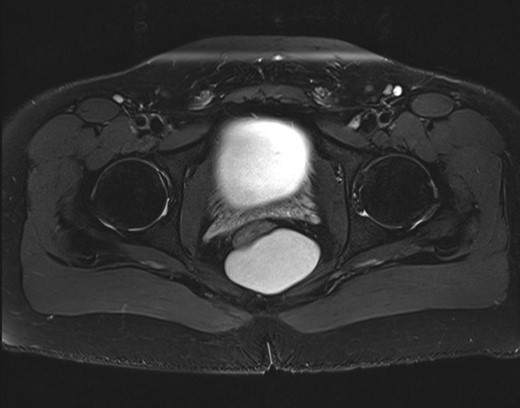

This is a case report describing the resection of a presacral cyst in a 23-year-old male patient. The cyst was discovered incidentally on CT scan of the abdomen and pelvis for evaluation of acute appendicitis (Fig. 1). The patient denied pain, bleeding, or change in bowel habits. He had no neurologic changes. A follow-up MRI was also performed (Fig. 2), and imaging was consistent with a congenital retrorectal cyst, with a tailgut cyst being favored. There was no evidence of bony involvement or invasion of other structures (Figs 1 and 2).

MRI pelvis demonstrating the retrorectal cysts, again with the rectum anterior and just to the right of midline.